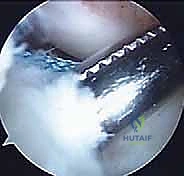

شكل 5: رؤية بالمنظار الجراحي بتقنية 4K عالية الدقة لمفصل الركبة من الداخل، مما يتيح للأستاذ الدكتور محمد هطيف رؤية أوضح للتشريح الدقيق وإجراء الجراحة بأقل قدر من التدخل الغازي.

- المنظار الجراحي: يتم إدخال كاميرا المنظار 4K عبر ثقبين صغيرين جداً في الركبة. يتم أولاً فحص المفصل بالكامل، ومعالجة أي تمزقات في الغضاريف الهلالية (خياطة الغضروف أو تهذيبه).

- الريادة في استخدام تقنية 4K: يُعد من أوائل الجراحين في اليمن الذين أدخلوا واستخدموا تقنية مناظير المفاصل بدقة 4K، مما يوفر رؤية مجهرية فائقة الدقة داخل ركبة الطفل، ويقلل من نسب الخطأ إلى الصفر تقريباً.